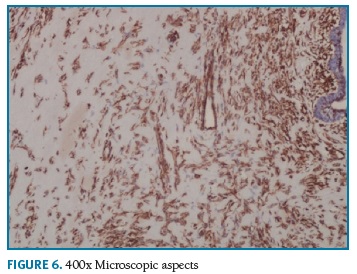

Definitive pathologic diagnosis of Pseudoangiomatous Stromal Hyperplasia (Fig. 4-5-6-7-8) was made on surgical specimen of mastectomy. The patient had regular follow-up at our department. Last visit was in May 2018, and no signs recurrence or contralateral breast cancer were diagnosed in those 11 years of follow-up.